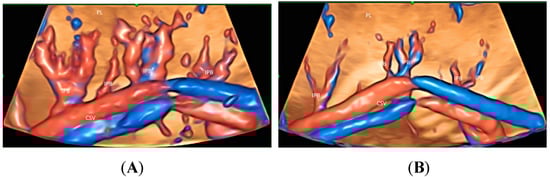

3. Placenta

| Placenta | Placenta accreta spectrum disorders | Chorionic and decidual vessels, Spiral artery jets Placental vascular anastomoses in twin pregnancies | Stem villous vessels |

| Placenta | High flow (CDFI) Chorionic and decidual vessels, Spiral artery jets (HDFI) | GBM | Different intraplacental vascularization in PAS, FGR, and PET |

| Twin | Placental vascular anastomoses (HDFI) Intraplacental branches of umbilical artery (HDFI) | GBM TUI | Placental anastomoses in TTTS Different intraplacental vascularization in selective FGR TRAP, Cord entanglement in monoamniotic twin |